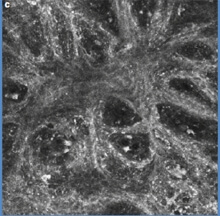

Examen en microscopie confocale ou biopsie virtuelle :

La microscopie confocale (confocal laser scanning reflectance microscopy) est un examen fait dans quelques centres spécialisés. Elle permet d’obtenir sur le vivant des images microscopiques de la peau en coupes autrefois seulement envisageable qu’après ablation chirurgicale de la lésion. En dehors de sa rareté, de son coût et de la formation hautement spécialisée nécessaire – la profondeur de l’examen est limitée à 0,3 mm sous la peau. Cet examen permet parfois d’éviter une biopsie inutile quand l’examen à l’oeil nu et au dermatoscope ne permettent pas de certitude. Cet examen est utile dans les localisations délicates ou une biopsie laisserait une marque – seins, organes génitaux, visage…

Microscope confoncal

mélanome en microscopie confocale

Microscope confoncal Vivascope® et mélanome en microscopie confocale